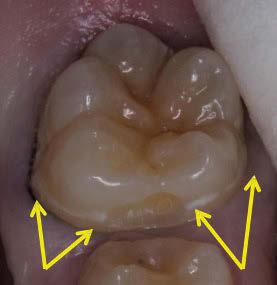

La exploración intraoral (figuras 4 a 8) revela una Clase II molar y canina completa, líneas 1/2 dentarias superior 0,5 mm e inferior 1 mm ambas desviadas hacia la derecha, los incisivos superiores excesivamente protruidos y vestibulizados (seguramente debido a la interposición del labio inferior), resalte de 13 mm y sobremordida 2/3 de corona. La discrepancia oseodentaria

inferior es de -3,5 mm y la curva de Spee de 4 mm.

Figuras 9-11.

vestibulizados (52º), e inferiores lingualizados (16 º). El perfil es extremadamente convexo.